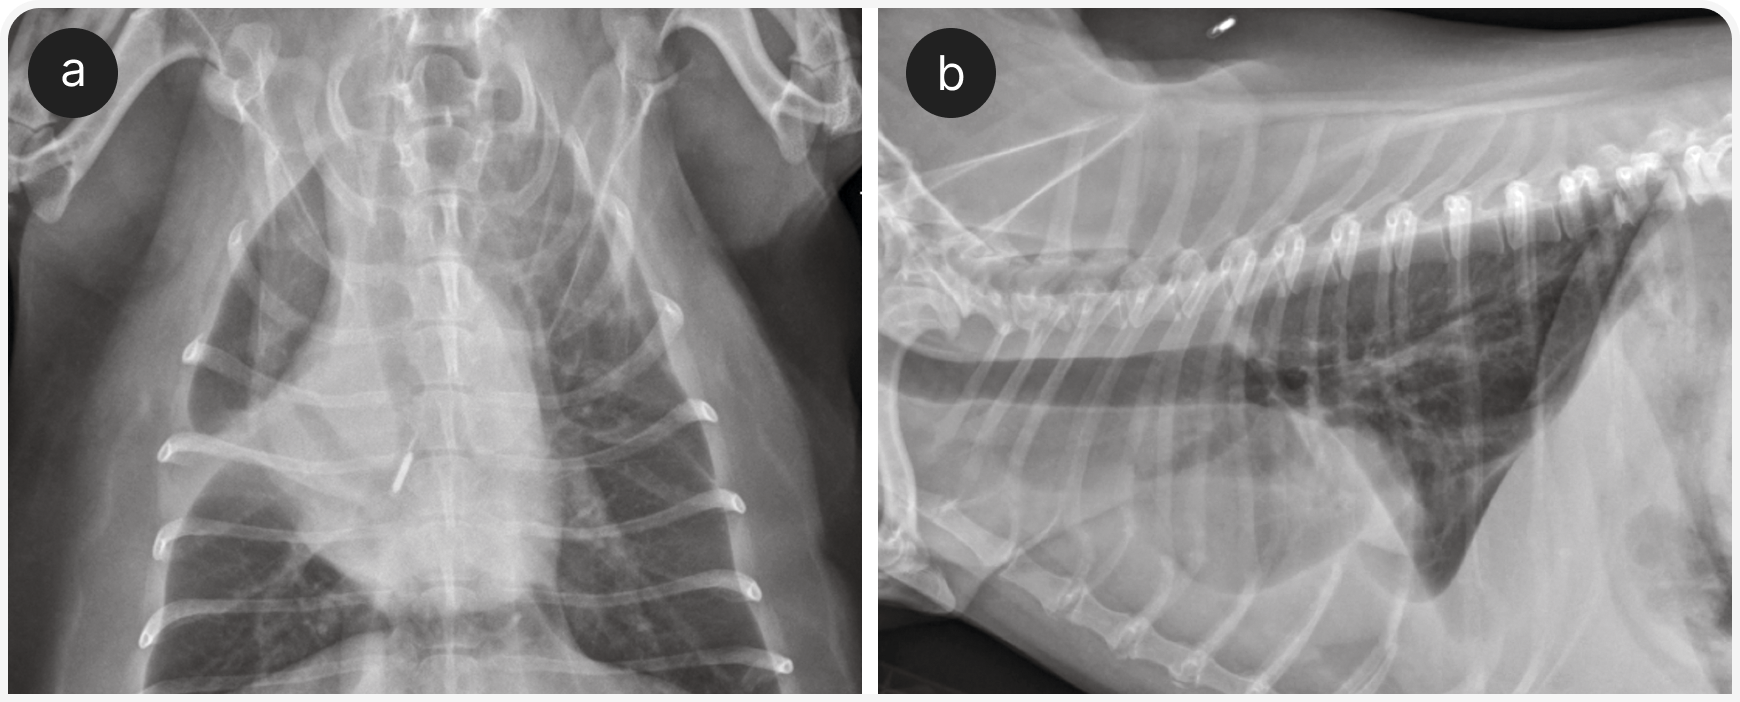

Этим пациентам могут быть полезны ингаляции кислорода и бронходилататоры, такие как тербуталин; однако у собак с подозрением на серьезные заболевания сердца следует соблюдать осторожность, так как тербуталин может увеличить частоту сердечных сокращений. После стабилизации рекомендуется провести рентгенографию органов грудной клетки для выявления картины бронхиального или бронхоинтерстициального поражения (Рисунок 2), хотя диагностическая чувствительность рентгенографии при заболеваниях бронхов у собак относительно низкая (2).

Рентгенография органов грудной клетки — основной метод диагностики у собак с заболеваниями легочной паренхимы (Рисунок 4), так же используется «прикроватное» УЗИ (POCUS), если это возможно, и эхокардиографией, если в списке дифференциальной диагностики высока вероятность заболевания сердца (Рисунок 5). В ожидании первоначального диагностического обследования можно рекомендовать компьютерную томографию органов грудной клетки и эндотрахеальный лаваж. По их результатам решают, следует ли ограничить лечение ингаляцией кислорода или нужно добавить антибиотики, диуретики, стероиды, бронходилататоры.